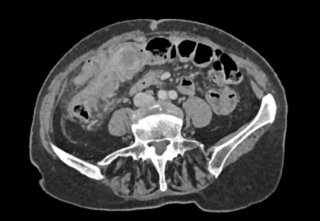

Case presentation

A 45-year-old man with no relevant past medical history presented with acute diffuse abdominal pain following a forceful sneezing episode. Physical examination revealed localized right-sided abdominal tenderness without peritoneal signs. Laboratory tests showed mild leukocytosis with normal inflammatory markers and hemoglobin. Contrast-enhanced computed tomography demonstrated a mesenteric hematoma associated with moderate hemoperitoneum and focal mural hypoenhancement of an ileal loop, without active arterial extravasation (Figure 1). Urgent surgical exploration revealed approximately 500 mL of hemoperitoneum, a large mesenteric hematoma, and an adjacent intestinal pseudodiverticulum (Figures 2-3). Segmental small bowel resection including the diverticulum was performed. Histopathological analysis confirmed fresh mesenteric hemorrhage and pseudodiverticular changes without evidence of malignancy, vasculitis, or vascular malformation. The postoperative course was uneventful, and the patient remained asymptomatic at six-week follow-up.